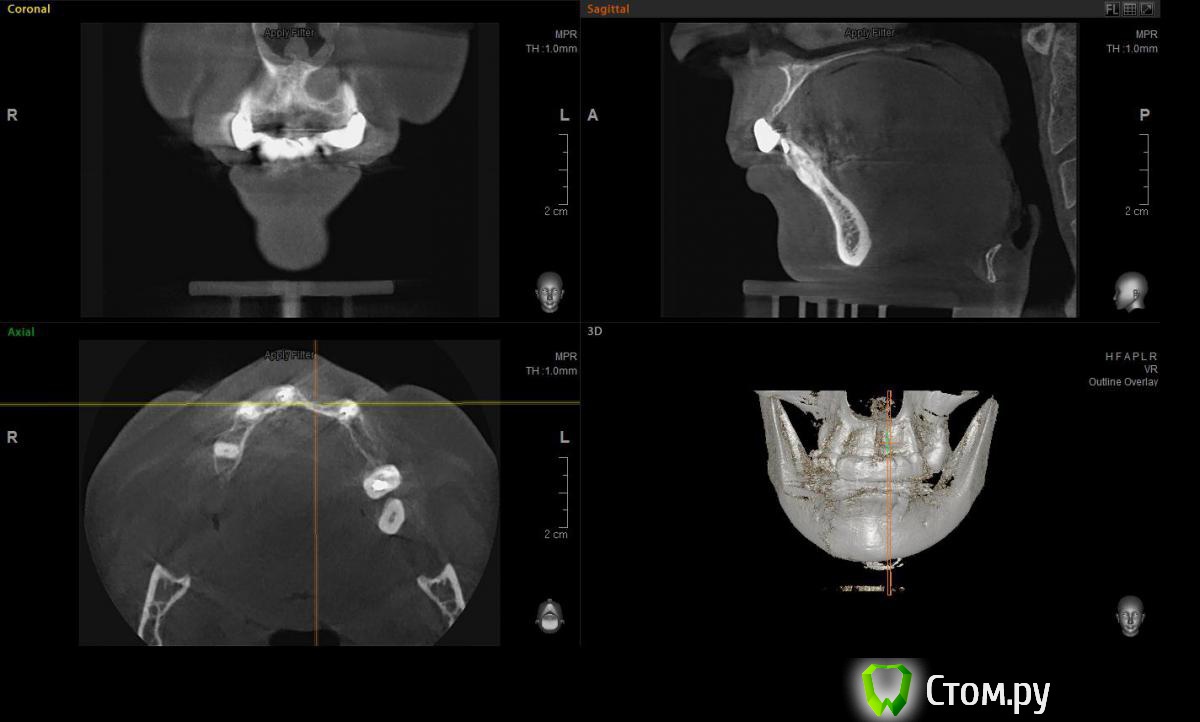

Евгений Ходыкин Опубликовано 23 июля, 2014 Поделиться Опубликовано 23 июля, 2014 Решили с пациенткой пока начать с в.ч. В планах имплантация в область отсутствующих 1.6, 1.4, 1.2, 2.1, 2.2, 2.4, 2.5. С 1.6 самому более менее все понятно, мануальных навыков хватит) Прошу помощи коллег относительно остальных областей. Фронт особливо печален... Забегая наперед скажу, что блоки еще не делал. Ауто точно пока брать не планирую, ибо нет даже теоретических навыков. Хочу начать все-таки с аллоблоков. У кого какие будут мнения, заранее спасибо) Ссылка на комментарий

Rafael_Gogyan Опубликовано 24 июля, 2014 Поделиться Опубликовано 24 июля, 2014 (изменено) фронт блоклибо сосиску (минимум 50% ауто) с одномоментной имплантациейв боковых отделах особых проблем не вижу. имплантация с НТР в обеих случаях + ССТ на ножке с нёба Изменено 24 июля, 2014 пользователем Rafael_Gogyan Ссылка на комментарий